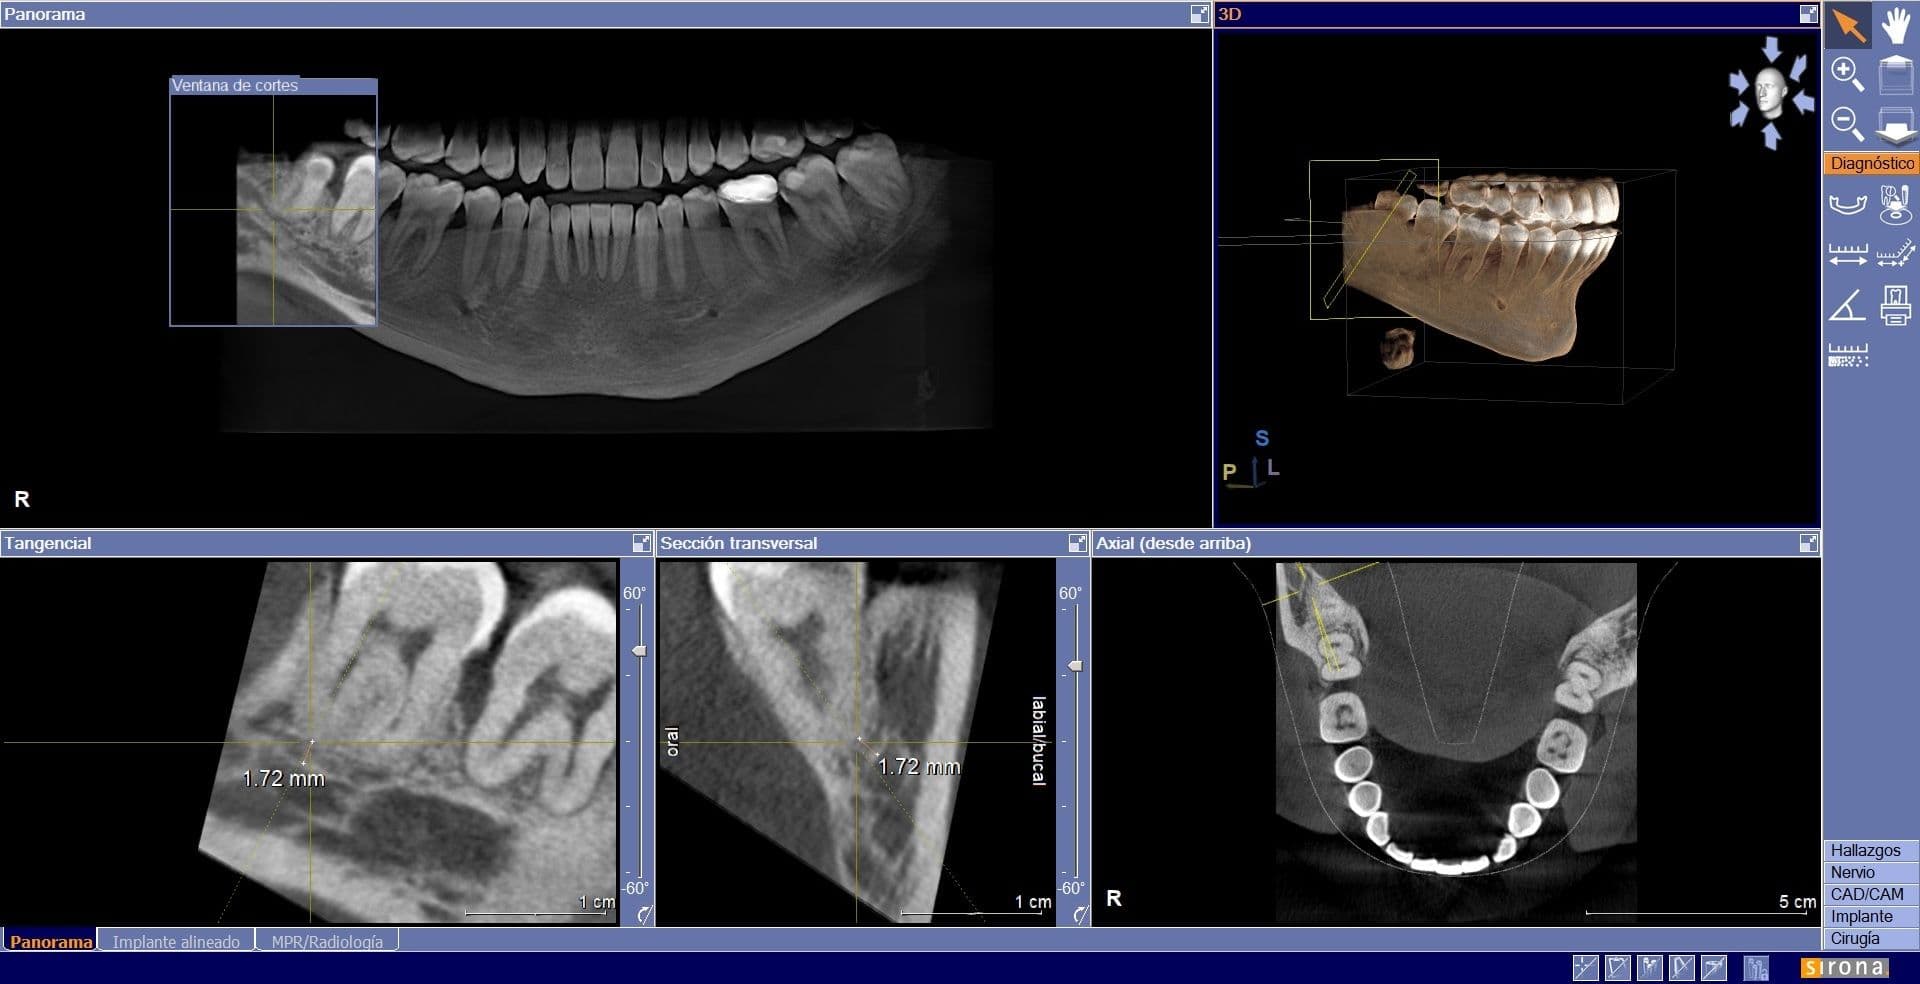

- Radiografía panorámica (ortopantomografía) gratuita (para primeras visitas).